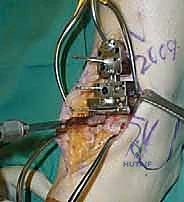

4. وضع أدلة القطع (Jig Placement and Alignment)

تعتمد دقة الجراحة على المحاذاة الصحيحة. يتم استخدام أجهزة توجيه متطورة (Jigs) تثبت على عظمة الساق باستخدام دبابيس معدنية. يتم التحقق من صحة الزوايا والمحاور باستخدام جهاز الأشعة السينية المباشر داخل غرفة العمليات (C-arm Fluoroscopy). يضمن الدكتور هطيف أن يكون القطع موازياً للأرض تماماً عند وقوف المريض.